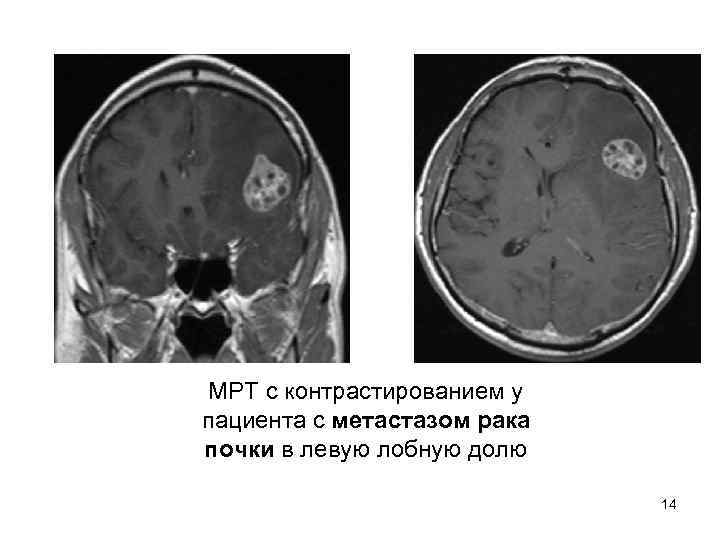

МРТ с контрастированием у пациента с метастазом рака почки в левую лобную долю 14